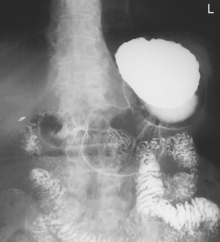

Fig. 9-31 AP supine Trendelenburg, upper GI (stomach) (Trendelenburg position best demonstrates hiatal hernia).